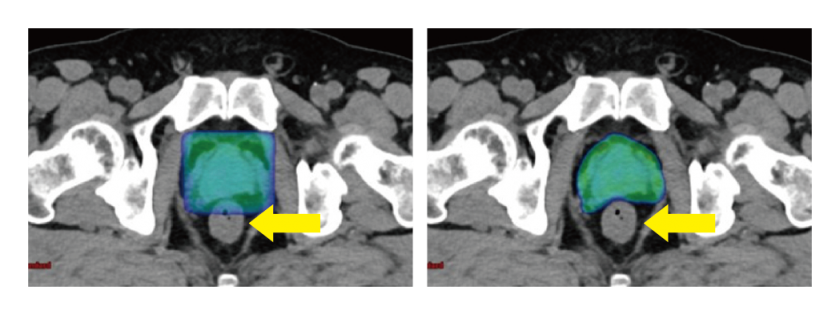

寡分割照射

放射線治療は通院回数が数十回に及ぶのが患者さんにとっては難点ですが、当院では1回当たりの線量を上げる「寡分割照射」によって通院回数を抑える取り組みに力を入れています。治療期間が短くなっても治療効果や副作用は変わらないという研究結果も出ており、数年前から乳がんに、昨年からは一部の前立腺がんに適用。乳がんの場合、25回の通院が16回に減る例もあり、通院の負担軽減に貢献しています。

高精度放射線治療では、照射位置を正確に決める必要があります。このため、毎回の治療時に画像を撮影して位置を正確に合わせ込む「画像誘導放射線治療」を行います。また、呼吸で動く部位には、所定の位置に患部が収まる時だけ照射する「呼吸同期照射」により精巧な治療を実現しています。左乳がんの術後照射では、深吸気息止め(DIBH)により心臓への照射を避けることができます。

乳がんの乳房温存術後照射や前立腺がんの根治照射には、1回あたりの線量を従来よりも増やし、通院回数を少なく抑える寡分割照射を導入しています。「線量が高いと副作用は?」「回数が少なくても効くの?」といった心配は要りません。経験豊富な放射線治療医師2名、放射線治療専門放射線技師や物理士、がん放射線療法看護認定看護師といった治療中の患者ケアや機器に精通した専門スタッフが常駐し、患者さん1人1人にしっかり時間をかけて対応するのが当院の強み。チームで患者さんの心身をサポートし、安心して放射線治療を受けられる環境が整っています。